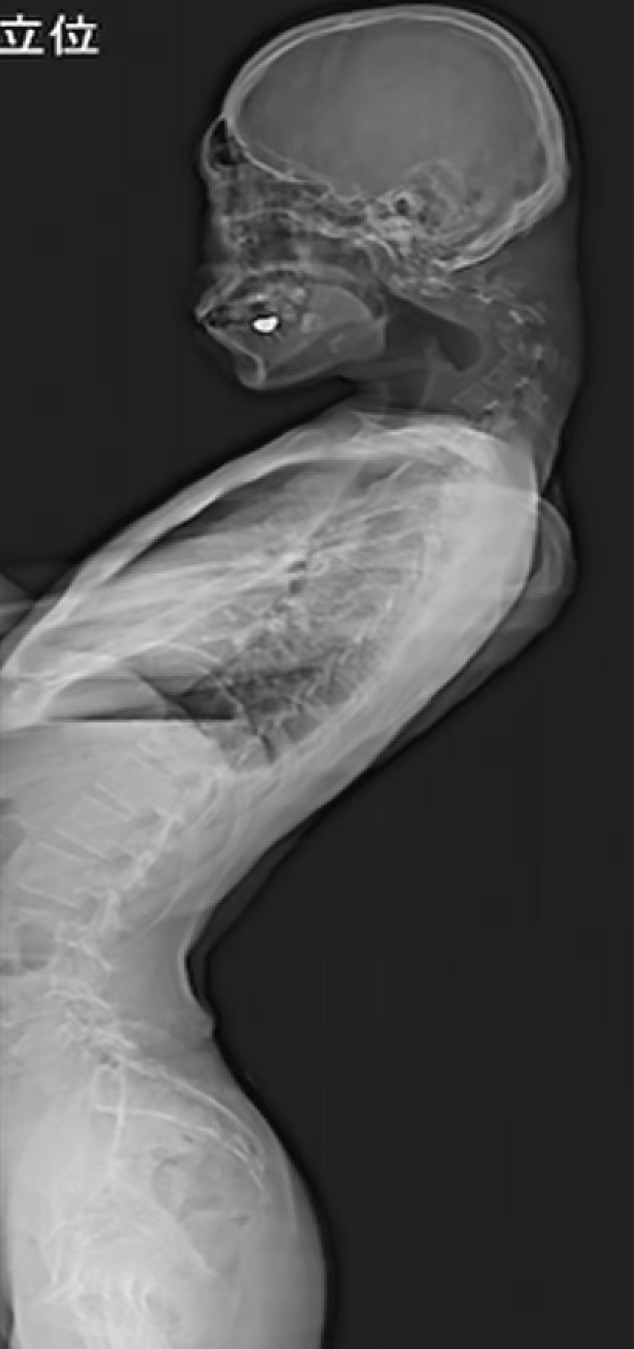

وأظهرت الصور الطبية تشوهات شديدة في فقرات الرقبة، أدّت إلى نمو أنسجة ليفية شبيهة بالندبات داخل العمود الفقري، في حالة تُعد من أشد مظاهر متلازمة الرأس المتدلي التي تم توثيقها.

وبعد فشل العلاج بأطواق الرقبة نتيجة شعور المريض بتنميل في الأطراف، لجأ الأطباء إلى إجراء عمليات جراحية معقدة، شملت إزالة أجزاء من الفقرات والأنسجة المتضررة، وتثبيت الرقبة بواسطة براغٍ معدنية وقضبان داعمة.

وبعد ستة أشهر من العملية، أظهر المريض تحسنًا تدريجيًا، وتمكن جزئيًا من رفع رأسه والنظر أفقيًا، إلا أن الأطباء أكدوا أن الضرر الواقع لن يُمحى بالكامل.